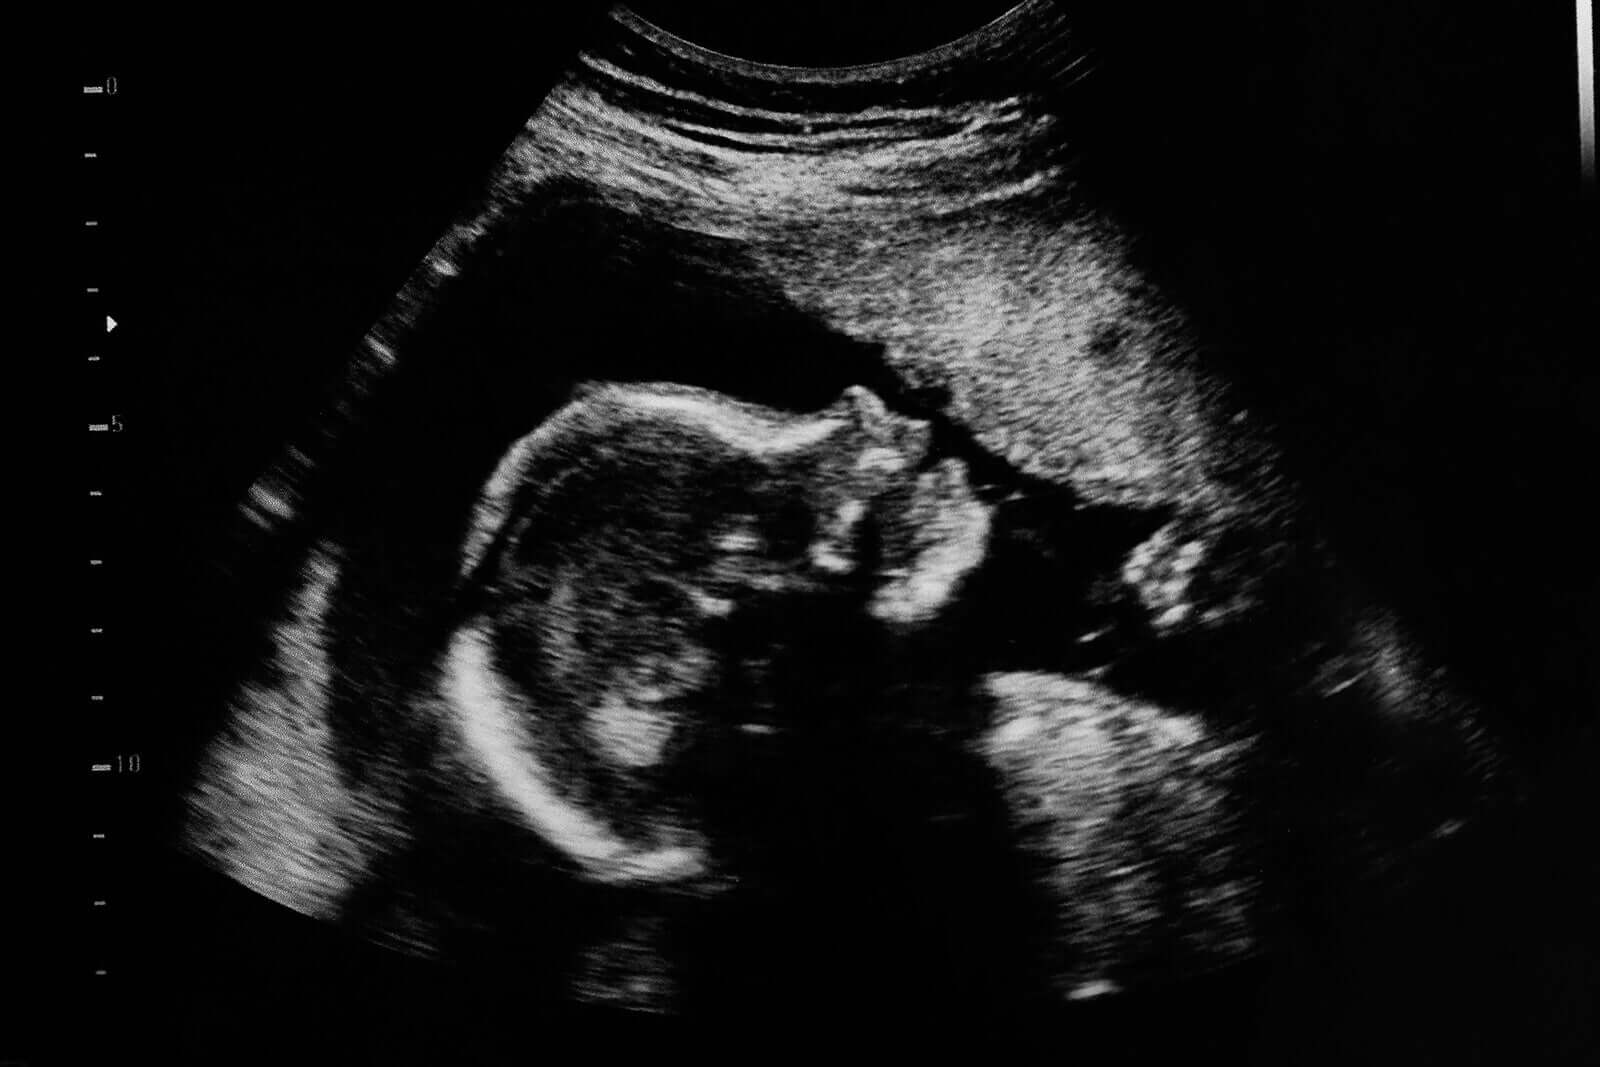

Een morfologische echografie is een niet-invasief onderzoek dat wil nagaan hoe het lichaam van de baby zich in de baarmoeder van de moeder ontwikkelt. Daardoor is het mogelijk bepaalde foetale pathologieën, zoals aangeboren misvormingen (Engelse link), tijdig op te sporen.

Hierbij wordt een speciaal apparaat gebruikt dat hoogfrequente geluidsgolven in de buik van de vrouw uitzendt.

Het geluid verspreidt zich door het vruchtwater. Het ‘botst’ tegen de verschillende structuren van de baby. Dit genereert een responssignaal (echo), dat een computer opvangt en weergeeft als een 2- of 3-dimensionaal beeld van de baby.

Echografieën dienen tijdens de hele zwangerschap vele doelen. Het belangrijkste doel van echografieën in het tweede trimester is echter te beoordelen hoe de verschillende organen van de baby zich gevormd hebben.